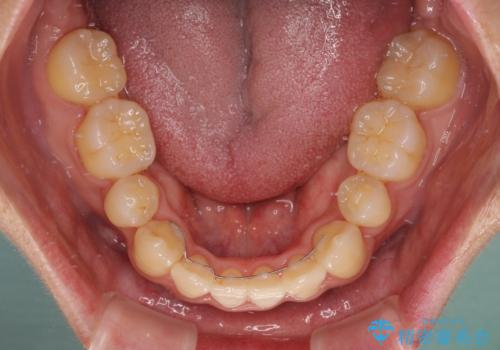

- 前歯の著しいデコボコを気にして来院された患者様です。

上顎の左右側切歯(前から2番目)が裏側に隠れいてる状態で、咬み合わせや清掃性に大きな問題が認められました。

叢生が著しいため、上下左右の小臼歯4本を抜去し、目立たないワイヤー装置にて矯正治療を行うこととしました。